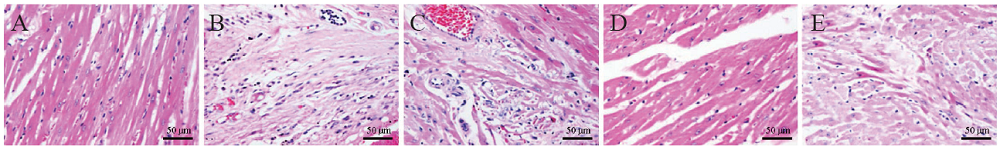

三、Masson染色观察大鼠心肌胶原组织变化

Masson染色结果显示,假手术组心肌组织形态完整、清晰,镜下视野呈紫红色,部分血管周围有少量呈蓝色的胶原组织;与假手术组比较,模型组心肌组织排列紊乱,呈紫红色的心肌组织明显减少,存在大量呈蓝色的胶原纤维,血管破碎,部分血管呈管腔狭窄和闭合现象;与模型组比较,柚皮素高剂量组和阿司匹林组均以紫红色心肌组织为主,蓝色胶原纤维大量减少,但柚皮素低剂量组仍存在较多的蓝色胶原纤维组织,且组织分布较紊乱;见图2

图2 各组大鼠心肌组织形态变化(Masson染色,×400)

A:假手术组;B:模型组;C:阿司匹林组;D:柚皮素高剂量组;E:柚皮素低剂量组

LVEF、LVFS、LVESD和LVEDD是评价心脏功能的常用指标。本研究结果显示,与假手术组比较,模型组LVEF和LVFS均降低,LVESD和LVEDD均增加,与模型组比较,阿司匹林组、柚皮素高剂量组和柚皮素低剂量组LVEF和LVFS增加,LVESD和LVEDD降低,表明心肌梗死后大鼠的心功能降低,出现明显的心室扩张和重构,阿司匹林、高剂量和低剂量的柚皮素处理后可改善大鼠的心脏功能,减轻心肌梗死后出现的失代偿性心室扩张。心肌细胞属于终末细胞,当发生心肌梗死时会造成不可逆转的组织缺血坏死,从而诱发机体产生自我保护反应,包括早期无菌性炎症反应和修复期成纤维细胞增殖、瘢痕及血管形成等活动,然而,持续的炎症损伤和过度的修复反而加剧细胞死亡和心肌收缩功能障碍,不利于心功能的改善[15,16]。本研究采用HE染色和Masson染色观察各组大鼠心肌梗死后心肌组织病理生理学改变,结果显示假手术组心肌组织结构正常、完整,心肌细胞分布均匀、有序,轮廓清晰可见,胞核与胞质边缘分明,血管管腔完整,仅部分血管周围有少量呈蓝色的胶原组织;与假手术组比较,模型组大鼠心肌组织排列紊乱、细胞轮廓不清晰,呈紫红色的心肌组织明显减少,存在大量呈蓝色的胶原纤维;与模型组比较,柚皮素高剂量组心肌组织排列较为整齐,血管管腔完整度较好,组织形态优于阿司匹林组和柚皮素低剂量组,Masson染色显示柚皮素高剂量组和阿司匹林组蓝色胶原纤维大量减少,但柚皮素低剂量组仍存在较多的蓝色胶原纤维组织,组织分布相对较紊乱,表明一定剂量的柚皮素能够抑制心肌梗死导致的组织损伤,减轻心肌组织胶原纤维的沉积。